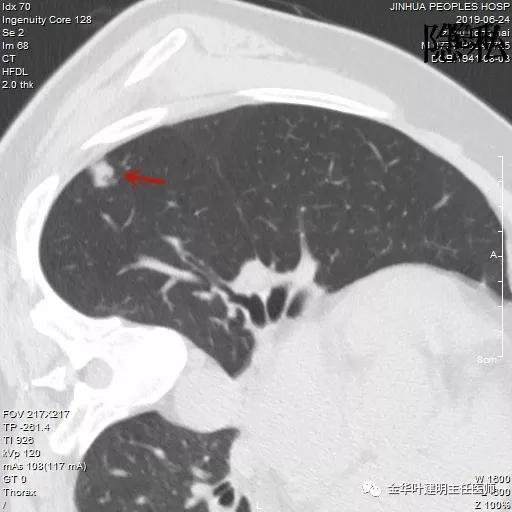

以上是2018年5月的片子,此处也呈空腔性病灶,但也点像是个肺大泡,因为绿色箭头所指处也有肺大泡。